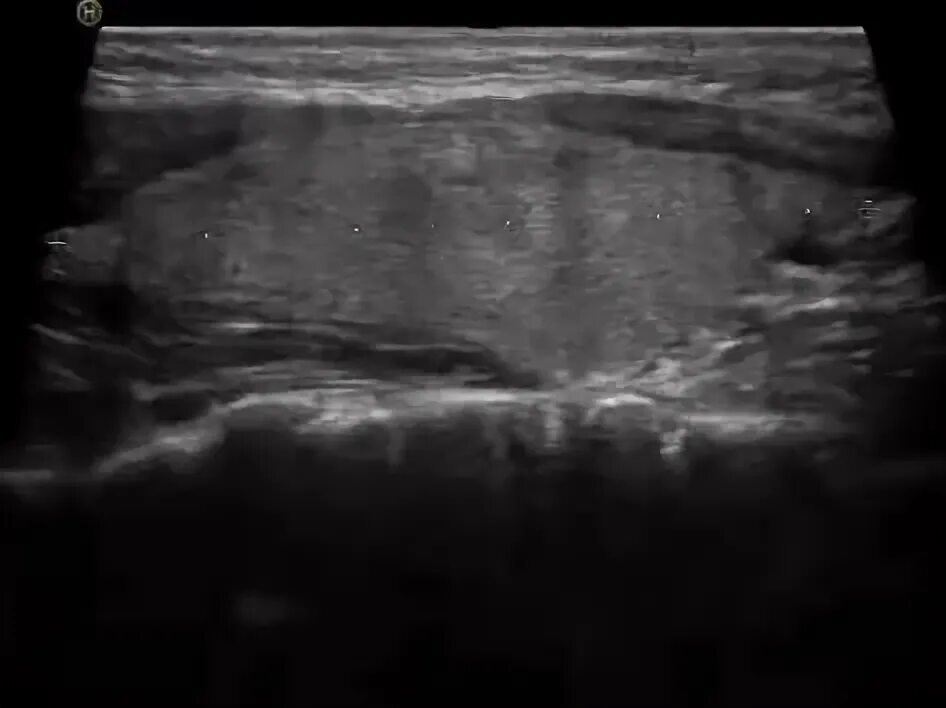

На фоне диффузных изменений